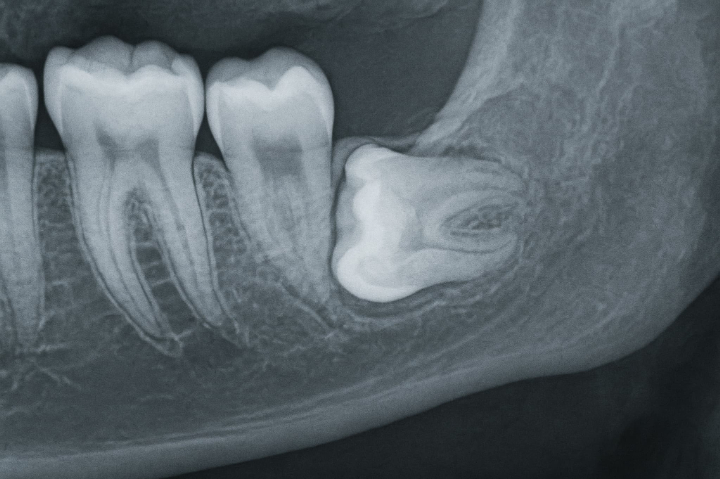

親知らずは、一般的に20歳前後に生えてくる最後の歯で、歯列の一番奥に位置します。親知らずがまっすぐ生えないケースも多く、顎のスペースが足りずに横向きや斜めに生えてくることも少なくありません。

横向きに生えた親知らずは、隣の歯に悪影響を与えたり、歯ぐきを圧迫して炎症を起こしたりする可能性があるため、抜歯が検討されることが一般的です。

まずはレントゲン撮影やCT撮影により、親知らずの状態(本数、向き、埋伏の程度など)を把握します。通常の抜歯では、専用の器具で歯冠を掴んで引き抜くというシンプルな手法ですが、横向きに埋まった親知らずの場合はこの方法はできません。歯冠と歯根を分割してから取り除くことになります。